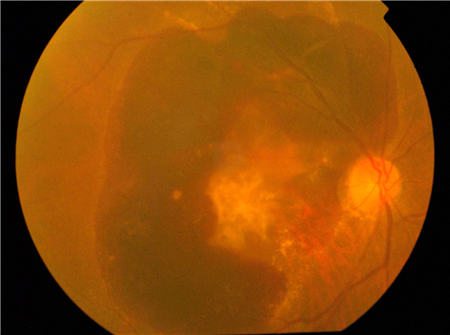

是的,眼里確實有“斑”,但并不是大家想象的那種皮膚上的斑,而是位于視網(wǎng)膜中心位置的黃斑區(qū),如果黃斑出了問題,可對視力造成嚴(yán)重影響,這時候就應(yīng)該去看眼科醫(yī)生了。

黃斑位于眼球后部視網(wǎng)膜中央的一塊小區(qū)域,是“掌管”中心視力以及精細視覺的重要部位,雖然大小跟一粒黃豆差不多,但如果這個部位發(fā)生了病變,中心視力也會受到嚴(yán)重影響。

黃斑變性就是黃斑病變的一種,也是比較常見的老年眼底病之一。一般來說,隨著年齡的增長,黃斑部視網(wǎng)膜細胞也會“變老”,發(fā)生黃斑變性的可能性也越大。除此之外,遺傳、吸煙、不良飲食習(xí)慣、高血壓、長期接觸猛烈陽光等因素,也會增加發(fā)生黃斑變性的風(fēng)險。

黃斑變性還分為“干性黃斑變性”和“濕性黃斑變性”兩種類型,在北京希瑪林順潮眼科醫(yī)院,主要通過“光學(xué)相干斷層掃描儀”來檢測黃斑變性,經(jīng)過診斷之后再根據(jù)患者病情來制定合理的治療方案。

一般來說,大多數(shù)的黃斑變性患者都屬于干性,對視力的影響也比較輕。對于干性黃斑變性,一般不需要治療,但由于干性黃斑變性還可能發(fā)生惡化,轉(zhuǎn)變成濕性黃斑變性。患者需要根據(jù)醫(yī)生建議定期隨訪,也可在專業(yè)醫(yī)生指導(dǎo)下使用葉黃素、玉米素、抗氧化維生素等補充劑,以延緩病情的發(fā)展。

而濕性黃斑變性嚴(yán)重情況下可致盲,需積極進行治療。希瑪眼科醫(yī)院針對濕性黃斑變性的治療,主要有光動力療法、類固醇玻璃體注射及抗血管內(nèi)皮生長因子玻璃體注射這幾種方式。有的患者可能只需要用到其中一兩種治療方式,也有的患者需要結(jié)合多種方式進行治療,具體使用何種治療方式,還需要根據(jù)患者的實際病情來“量身定制”。